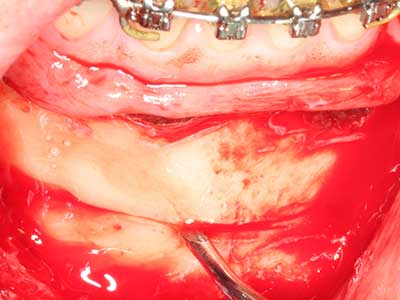

Si es preciso realizar intervenciones quirúrgicas en las que el hueso está en contacto directo con estructuras sensibles, como son los vasos sanguíneos o los nervios, los instrumentos rotativos presentan un enorme potencial de provocar lesiones iatrogénicas. Así, precisamente en la representación de nervios después de una lesión iatrogénica, o en el transcurso de la lateralización de un nervio para resecciones, reconstrucciones o incorporación de implantes, los equipos piezoeléctricos pueden resultar muy útiles para preparar la tapa ósea y retirar las partes de tejido duro cercanas al nervio (fig. 17-20). Por lo general, un ligero contacto del cordón nervioso con el inserto piezoeléctrico no tiene consecuencia alguna; ahora bien, un procedimiento poco cuidadoso con movimientos tipo sierra o piezas de trabajo sobre la base ósea aún existente puede provocar lesiones nerviosas temporales o incluso permanentes. Con todo, el riesgo de sufrir una lesión de este tipo se considera significativamente inferior que en los casos en los que se utilizan sierras y fresas (Pereira, Gealh et al. 2014).